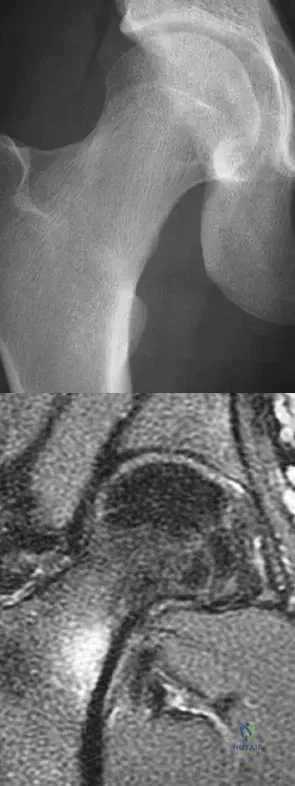

A 21-year-old collegiate female cross-country athlete reports right hip pain that begins about 12 miles into a run, followed by pain resolution when she discontinues running. However, each time she tries to resume a running program, she experiences recurrence of pain deep in the anterior groin. A plain radiograph and MRI scan are shown in Figures 8a and 8b. Management should consist of